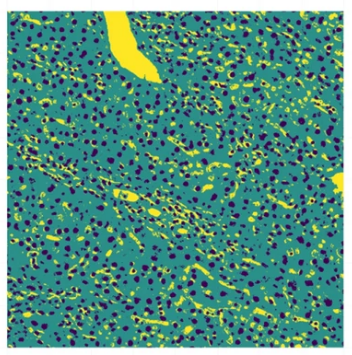

Reinterpretation of histological images as categorized rasters and their use for disease classification (e.g., liver cancer)

Kendall et al., 2020, 10.1038/s41598-020-74691-9